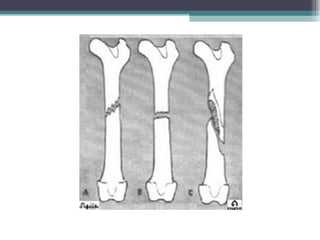

Fraturas Quanto ao traço de fratura   Incompleta: ocorre a lesão óssea, mas não rompe a continuidade óssea; tipo de ocorrência comum em crianças.  Completa: os fragmentos ósseos perdem a continuidade, ficando desviados ou não.

Fraturas Deformidade  O segmento fraturado apresenta angulações, rotações e encurtamentos evidentes à simples observação da vítima, comparando-se o membro lesado com o não afetado.  Impotência funcional  A fratura impede ou dificulta os movimentos, devido à dor e à alteração músculoesquelética, no que diz respeito à anatomia.  Crepitação óssea  Sensação audível e palpável causada pelo atrito entre os fragmentos ósseos. Não deve ser reproduzida intencionalmente, porque provoca dor e aumenta a lesão entre os tecidos vizinhos à fratura.

Fraturas Quanto aotraço de fratura Incompleta: ocorre a lesão óssea, mas não rompe a continuidade óssea; tipo de ocorrência comum em crianças. Completa: os fragmentos ósseos perdem a continuidade, ficando desviados ou não.